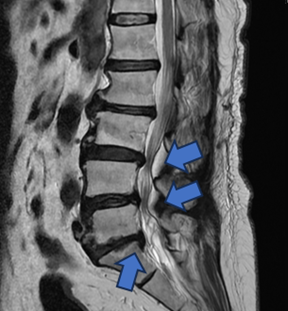

手術以間接減壓的方式,從後腹腔進入(紅色箭頭),有別傳統從脊椎腔(藍色箭頭)切入,因此能夠不破壞骨骼不撥弄脊椎神經,大幅減低神經損傷機率。官方提供

【手術前及手術後】手術前有脊椎滑脫不穩定及脊椎狹窄造成神經壓迫(左圖)。手術後除了重建椎間高度,也將腰椎的生理曲線重建為較理想的前凸狀態(右圖)。官方提供